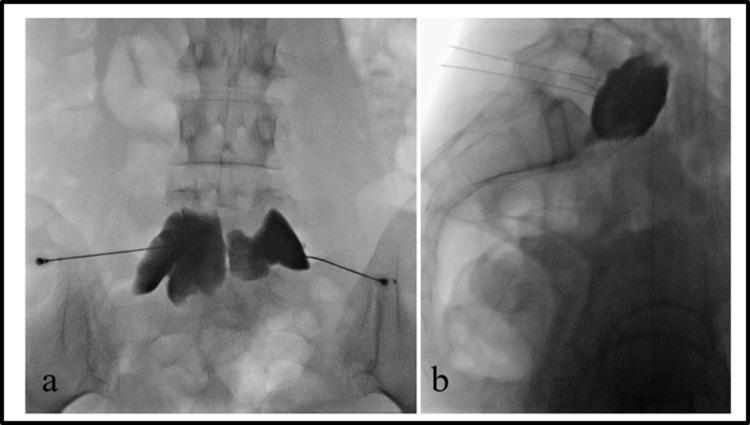

在患有癌症相关疼痛的患者中,10%至20%的患者按照世界卫生组织的三阶梯指南无法实现充分控制。因此,对于这些病例,有人建议采取包括介入治疗方法在内的“第四步”。系统评价支持早期使用介入程序来治疗难治性癌症疼痛、控制症状并防止阿片类药物剂量增加。有强有力的证据表明腹腔神经丛或内脏神经松解术、椎体成形术、后凸成形术和鞘内药物递送的有效性。已发现这些程序与症状负担减轻和阿片类药物消耗减少、生活质量改善相关,并且被认为对生存可能有积极影响。几项研究建议在更早阶段使用特定的介入技术,甚至可能在首次考虑阿片类药物治疗时就使用。相反,将这些选择留作最后的镇痛资源可能并不可取,因为这些程序可能给病情过重的患者带来的负担很大。本综述的目的是收集已发表的关于使用介入治疗难治性癌症疼痛的现有证据,特别关注比较早期与晚期适应症。检索结果显示专门针对这个问题的文章数量和质量都非常低。证据数量稀少,无法进行系统分析。本文提供了关于在疾病早期将介入技术纳入临床指南的潜在益处的详细叙述性描述。

Systematic review and meta-analysis of celiac plexus neurolysis for abdominal pain associated with unresectable pancreatic cancer.腹腔神经丛阻滞术治疗不可切除胰腺癌相关腹痛的系统评价和荟萃分析

Pain Pract. 2022 Sep;22(7):652-661. doi: 10.1111/papr.13143. Epub 2022 Jul 1.